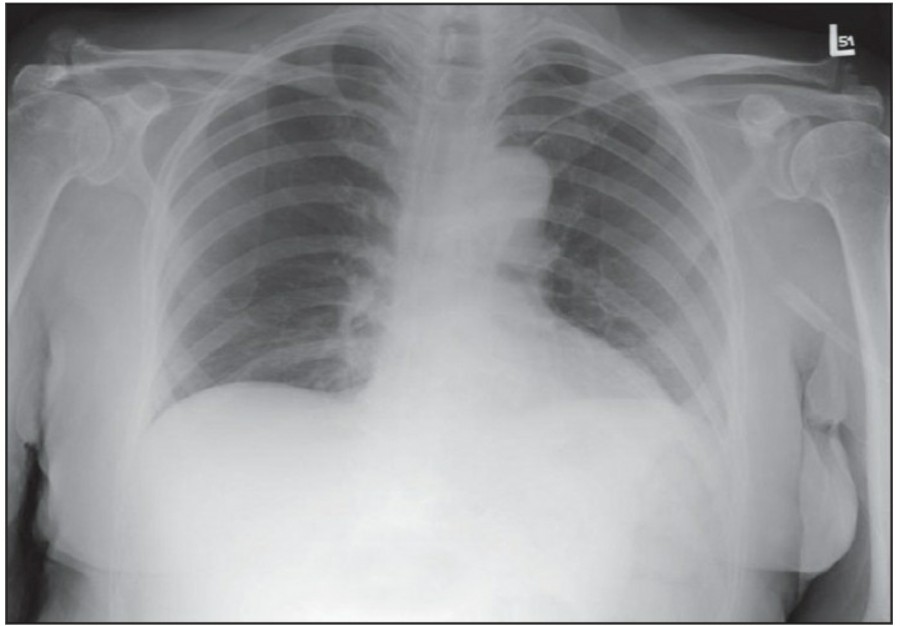

중환자실에서 일반적으로 PA chest X ray는 거의 시행하지 않으며, 주로 AP(anteroposterior) chest X ray를 시행한다. AP CXR은 upright position에서 최대 흡기 시 patient-to-x-ray plate가 72inches(182.88cm)지만, 중환자는 움직임이 제한되므로 supine 혹은 sitting position에서 시행하며 그 거리는 40inches(101.6cm) 정도다.

이렇게 얻어진 image는 gravitational and geometrical effect로 인해 mediastinum과 heart가 확대되어서 보이는데, 더욱이 supine position은 pulmonary vasculature의 physiology를 변화시켜서 혈류가 lung apex로 흐르게 한다-이렇게 얻어진 형태는 PA CXR에서는 비정상으로 간주되지만 AP CXR에서는 정상이다. Supine position은 pleural effuson과 air space shadowing의 감별, pneumothorax 발견을 힘들게 한다.

중환자는 협조가 되지 않거나 수술 후 통증 때문에 full inspiration이 쉽지 않으므로 X ray image를 얻기가 어렵다., 따라서 basialr atelectasis와 pulmonary edema의 진단이 어렵고, heart와 mediastinum의 크기가 정확히 나타나지 않게 된다.